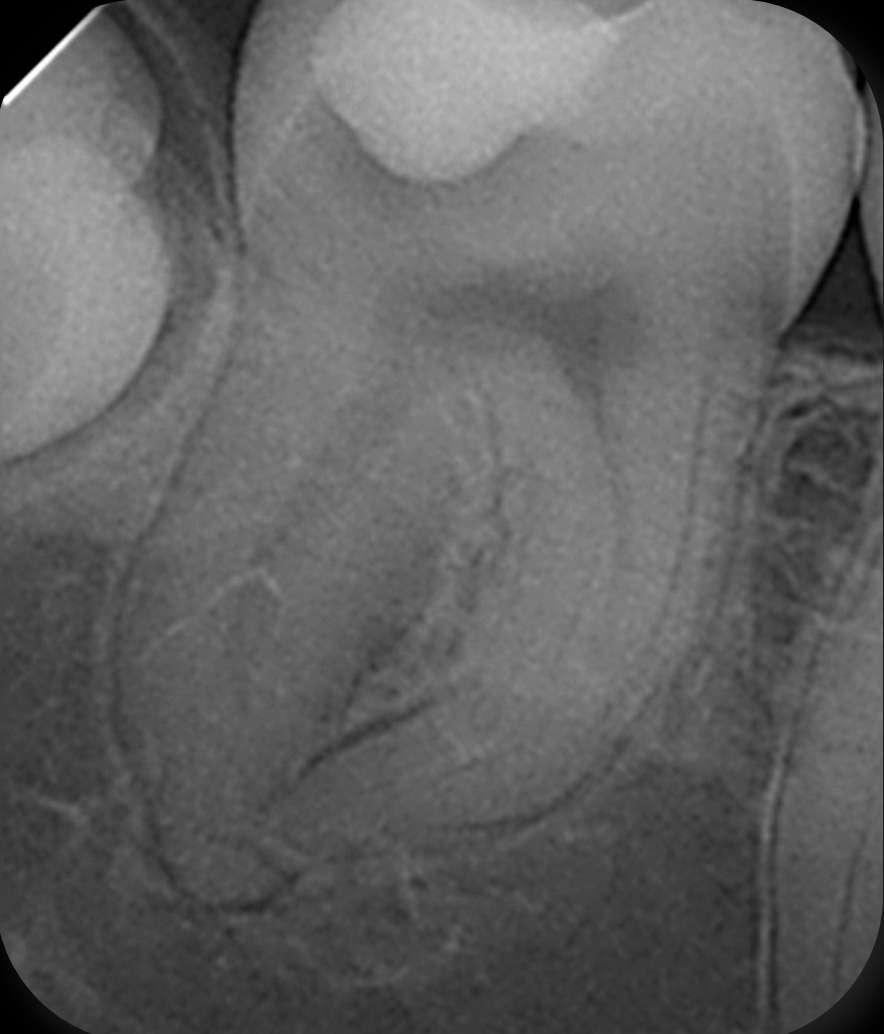

Fig. 5: Angulated post-op radiograph of the mandibular right second molar demonstrating the curvature of the mesial canals and the dense 3D obturation achieved up to working length.

For obturation, a modified warm vertical compaction technique was applied at 150 °C using a customised gutta-percha cone. For the final seal and in support of the healing process, ROEKO GuttaFlow bioseal (COLTENE) was chosen. The angulated postoperative radiograph revealed dense filling of all canals and of an additional lateral canal in the distal root, confirming that the modified warm compaction technique and GuttaFlow bioseal had effectively sealed the entire canal system (Figs. 4 & 5).